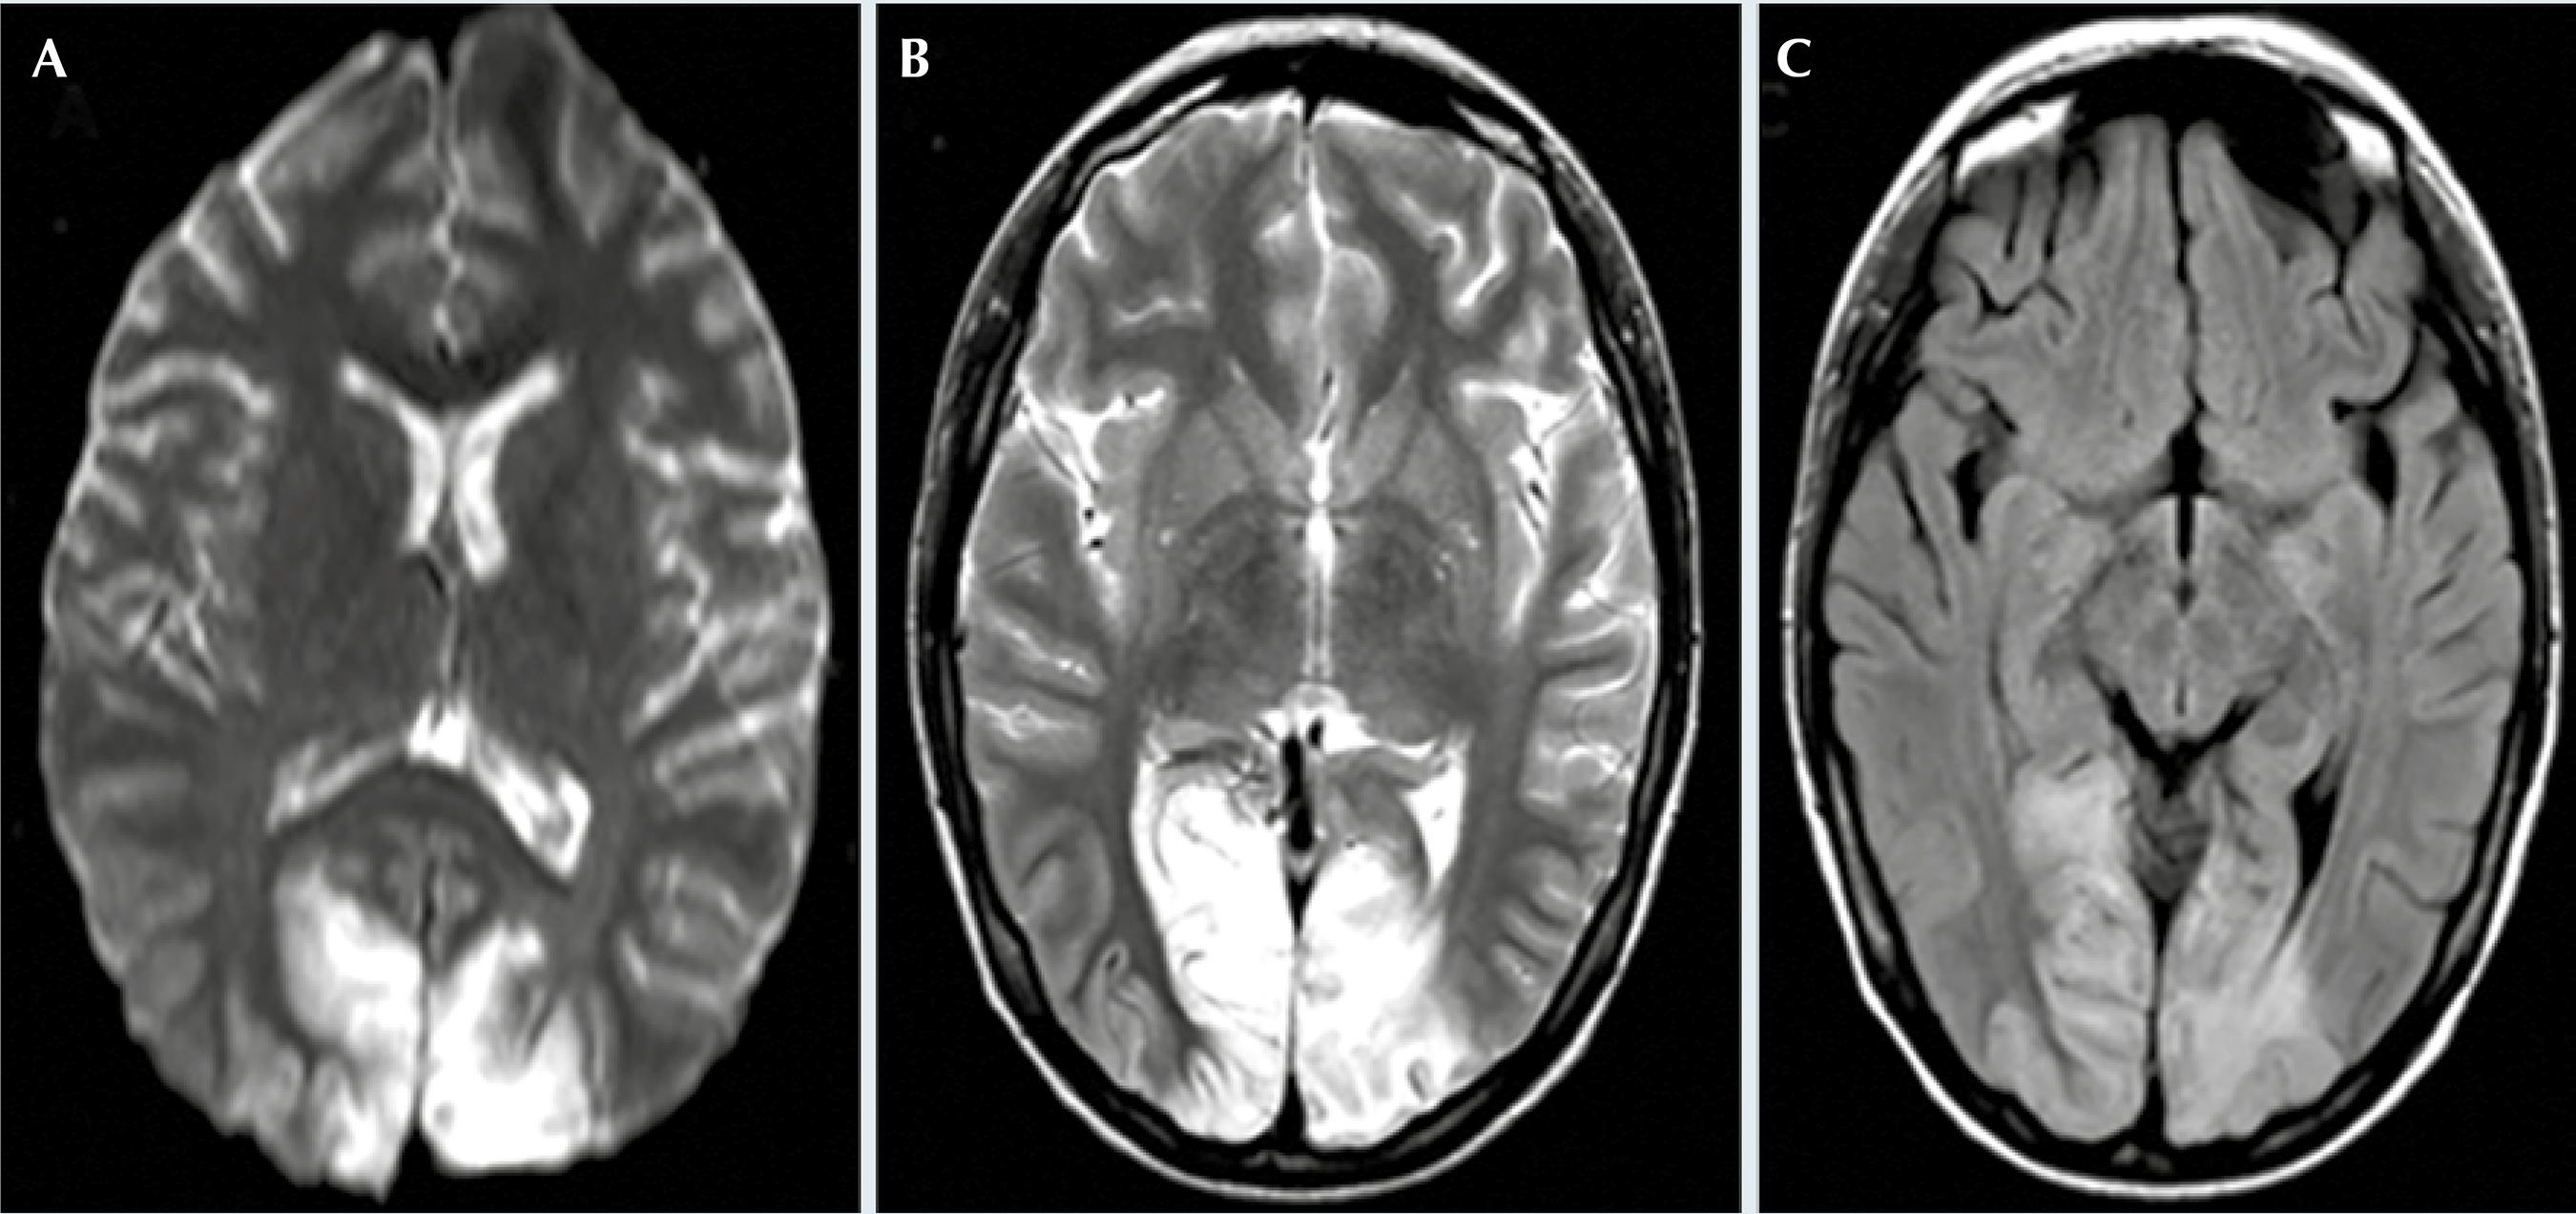

Figura 2 Resonancia magnética de encéfalo realizada en la unidad de cuidados intensivos en secuencias A) difusión axial, B) T2 axial, C) FLAIR axial donde se observa restricción en secuencia de difusión, hiper-intensidades en regiones occipitales bilaterales en secuencia T2 y FLAIR, respectivamente.

Una nueva resonancia magnética en la unidad intensiva pediátrica mostró que persistía hiperintensidad mal definida en región occipital izquierda con extensión a región occipital centrolateral y contralateral con pérdida de relación de sustancias y restricción occipital bilateral en secuencia de difusión (Figura 2), los ácidos láctico y pirúvico se reportaron normales, así como un estudio inmunológico ac anti P-Ribosomal, ac antinucleosomas, ac antifosfolípidos, cardiolipina, B2 glicoproteína, fosfatidilserina, fosfatidilinositol, etc. Se inició terapia esteroidea con metilprednisolona a dosis de 1 g/día, hubo mejoría clínica posterior a 5 bolos.

En nuestra paciente llaman la atención las manifestaciones clínicas visuales, debidas al territorio afectado en la circulación cerebral posterior. Los datos de imagen en nuestro caso son similares a lo descrito en la literatura de acuerdo con Xie y sus colaboradores, donde los hallazgos en la resonancia magnética en pacientes con MELAS han demostrado lesiones que afectan predominantemente la sustancia gris sin un territorio vascular específico las cuales son hiperintensas en T2 y FLAIR.8